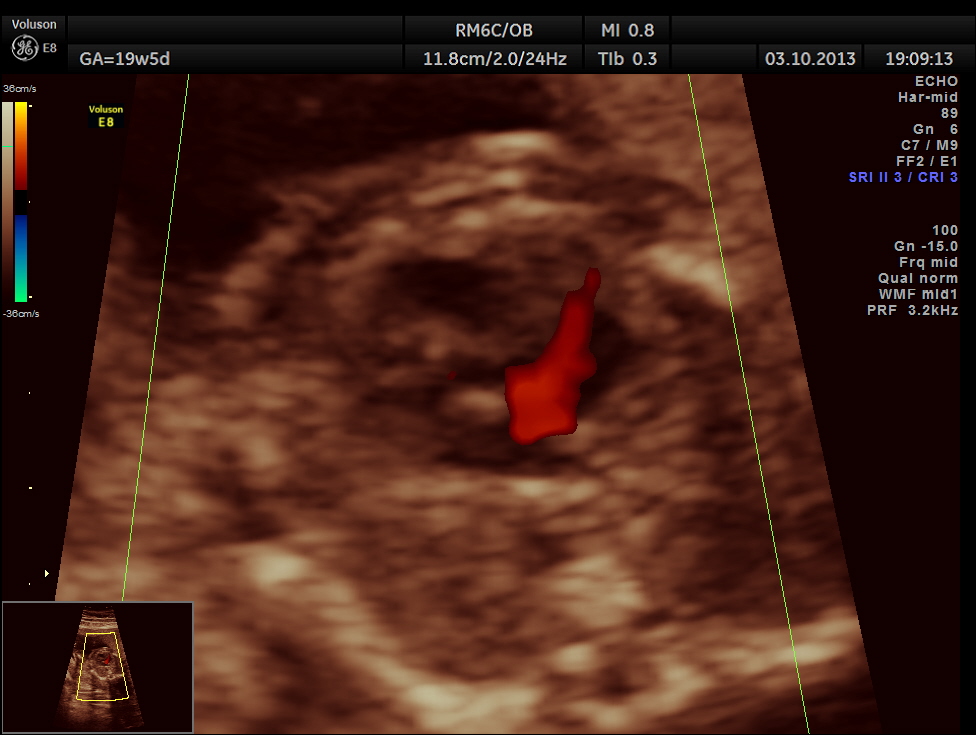

The following picture shows the reversal of flow in the foramen ovale , which according to some authors is a salient diagnostic feature of co-arctation of aorta.

The diagnosis offered was PROBABLE CO-ARCTATION OF AORTA .